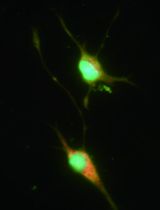

Macrophages are involved in many key physiological processes and complex responses such as inflammatory, immunological, infectious and neoplastic diseases. The appearance and activation of macrophages are thought to be rapid events in the development of many pathological lesions, including malignant tumours, atherosclerotic plaques, and arthritic joints. This has prompted recent attempts to use macrophages as novel cellular vehicles for gene therapy, in which macrophages are genetically modified ex vivo and then reintroduced into the body with the hope that a proportion will then home to the diseased site. Here, we describe a protocol for preparing monocyte-derived macrophages (MDM) and arming these with oncolytic viruses (OV) as a novel way for delivering anti-cancer therapies. In this approach, proliferation of macrophages co-transduced with a hypoxia-regulated E1A/B construct and an E1A-dependent oncolytic adenovirus, is restricted to prostate tumour cells using prostate-specific promoter elements from the TARP, PSA, and PMSA genes (Muthana et al., 2013; Muthana et al., 2011). When such co-transduced cells reach an area of extreme hypoxia (like that found in tumours), the E1A/B proteins are expressed, thereby activating replication of the adenovirus. The virus is subsequently released by the host macrophage and infects neighboring tumour cells. The virus then infects neighboring cells but only proliferates and is cytotoxic in prostate tumour cells. OV kill cancer cells by a number of mechanisms, including direct lysis, apoptosis, autophagy and shutdown of protein synthesis, as well as the induction of anti-tumoural immunity. Using macrophages to deliver OV ensures that they are protected from the many hazards they face in circulation including neutralizing antibodies, complement activation and non-specific uptake by other tissues such as the liver and spleen.